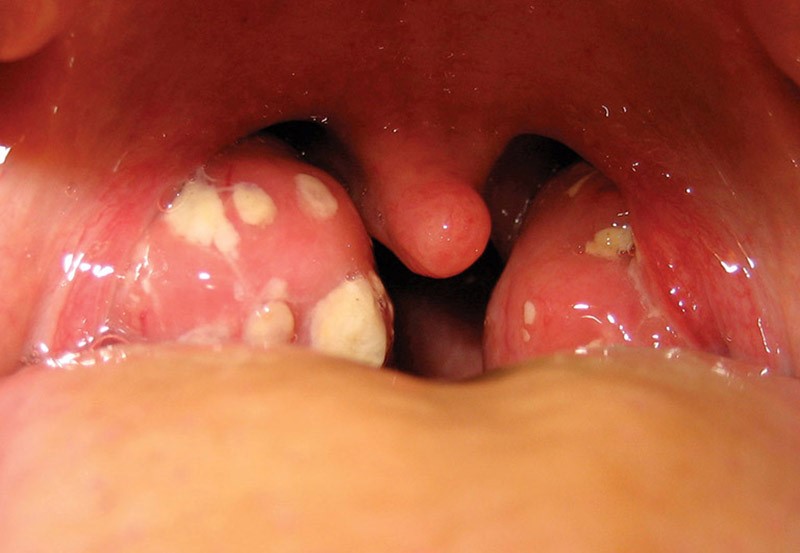

Amidan sưng đỏ

Có đốm mủ trắng ở amidan (đây là dấu hiệu đặc trưng nhất)

Amidan sưng to, có đốm mủ trắng